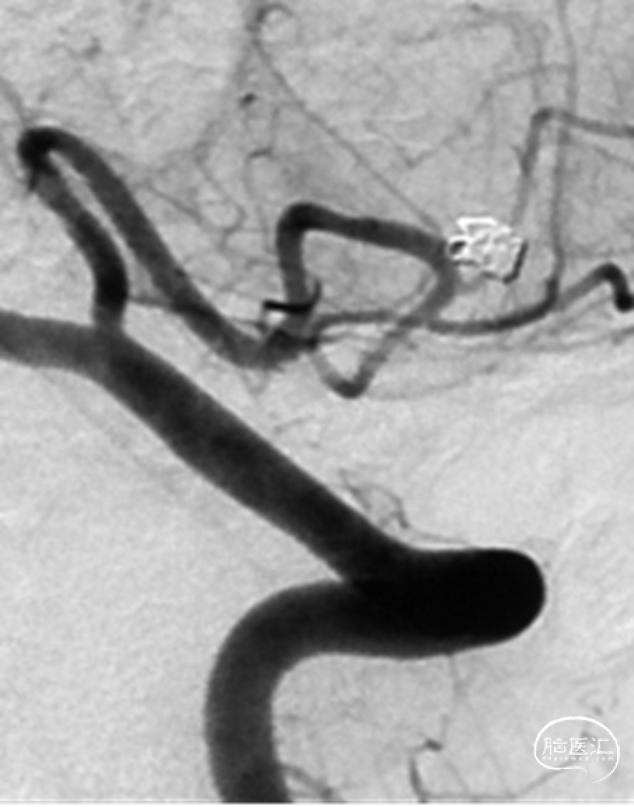

行单纯弹簧圈栓塞及载瘤动脉闭塞术。术后即刻造影提示动脉瘤不显影,载瘤动脉闭塞,侧枝代偿良好

2、影像学随访:一年后的随访影像显示动脉瘤完全不显影。

一年后的随访影像